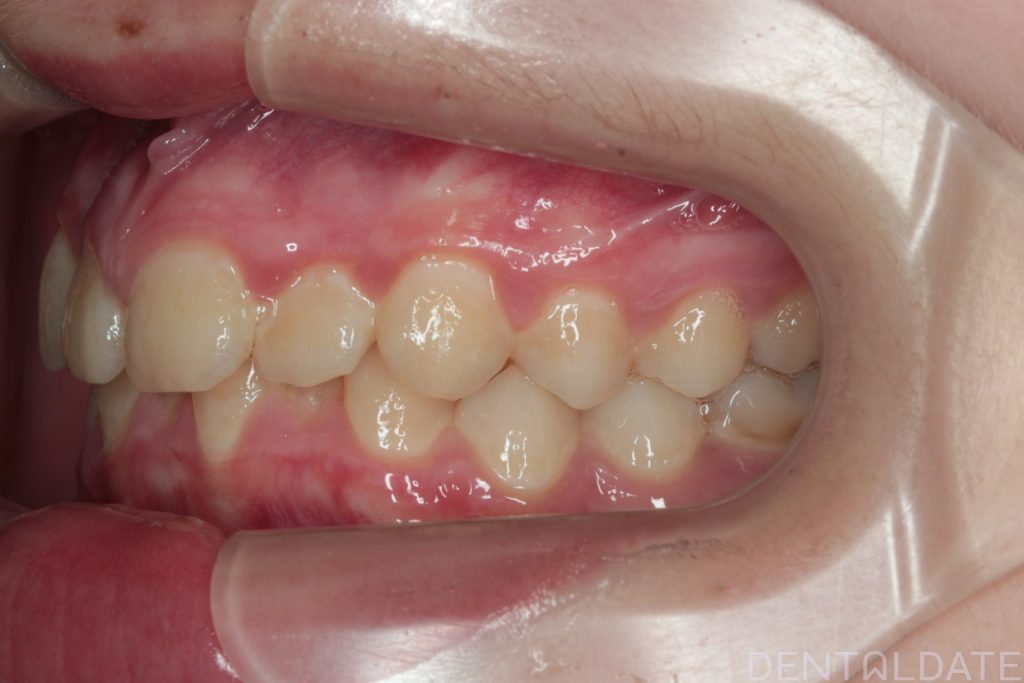

The patient presented with a complaint about an unattractive smile.

The central aesthetic lines did not match, and the bite was incorrect.